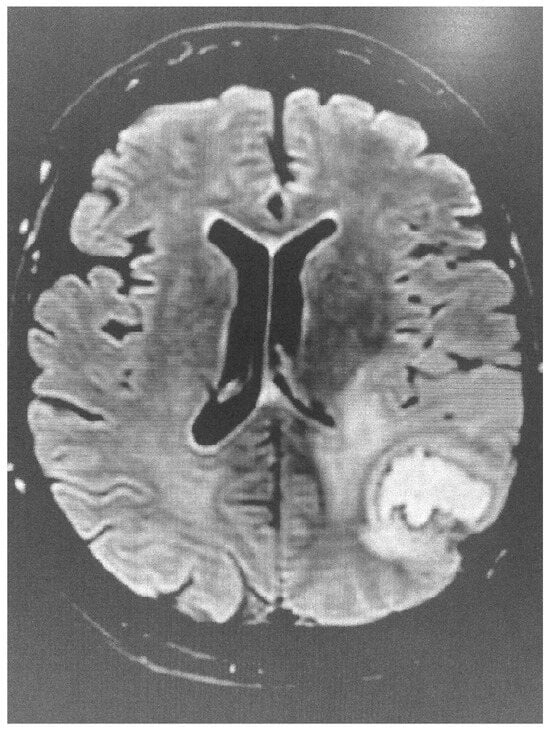

CMR can visualize the typical regional wall motion abnormalities characteristic of TTS, such as apical or mid-ventricular ballooning. In addition, it can detect the presence of myocardial oedema and fibrosis (tissue characterization). The presence of oedema in the absence of positive late gadolinium enhancement (LGE), which represents replacement fibrosis, is typical of TTS. However, positive LGE can be found in patients with a mild cardiac enzyme elevation [3]. CMR may facilitate the differential diagnosis of other cardiac conditions, such as myocardial infarction, myocarditis, and ischemic and non-ischemic cardiomyopathies.

During the acute phase of TTS, CMR is recommended in doubtful cases, especially in those where different therapeutic protocols are needed, as in MINOCA or myocarditis. Furthermore, in the post-acute TTS phase, it is recommended in all patients within 2 months, if they have persisting ECG and/or regional wall motion abnormalities in the echocardiographic evaluation, in order to finally document the diagnosis of TTS [32]. CMR images of TTS are presented in Figure 3 and Figure 4.

Figure 4. Short axis LGE image showing lack of replacement fibrosis in the same patient.